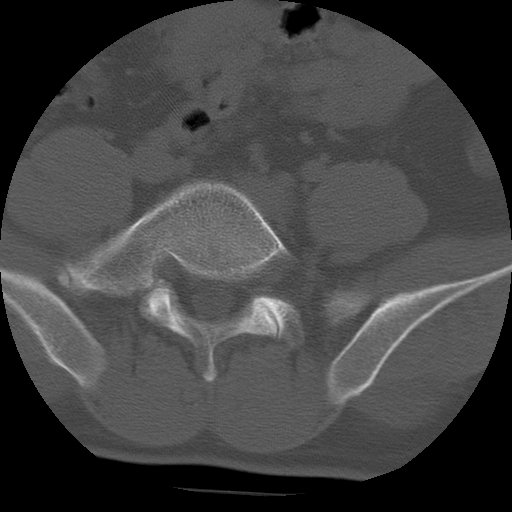

标题: CT24390:男,23岁,腰痛就诊。

男,23岁,腰痛就诊。

腰5右侧横突肥大伴假关节形成.

支持!图像少,再往下扫骶髂关节面,椎小关节毛糙,青年男性需排除as,实验室查b27。

腰5右侧横突肥大伴假关节形成

腰5右侧横突肥大伴假关节形成!支持!

l5右侧横突肥大伴假关节形成。

腰椎骶化或骶椎腰化常见。